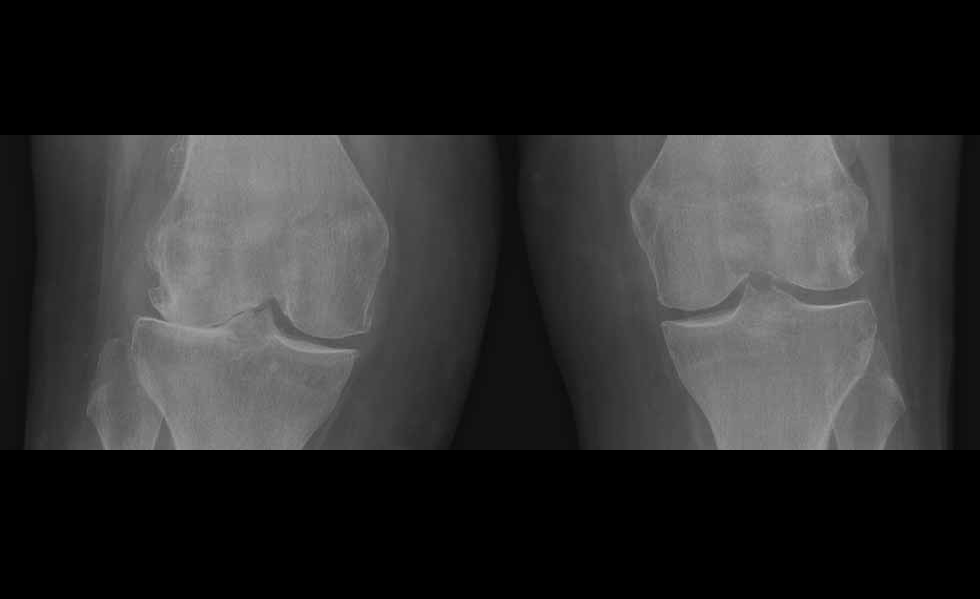

At Sussex Knee Surgery we provide a comprehensive range of treatment for knee problems of all types from our clinics and operating theatres in Sussex on the south coast of England.

Our services are lead by Simon Palmer who is a Consultant Orthopaedic Surgeon with specialist training and experience in all aspects of knee surgery, including minimally invasive surgery and partial knee replacement.